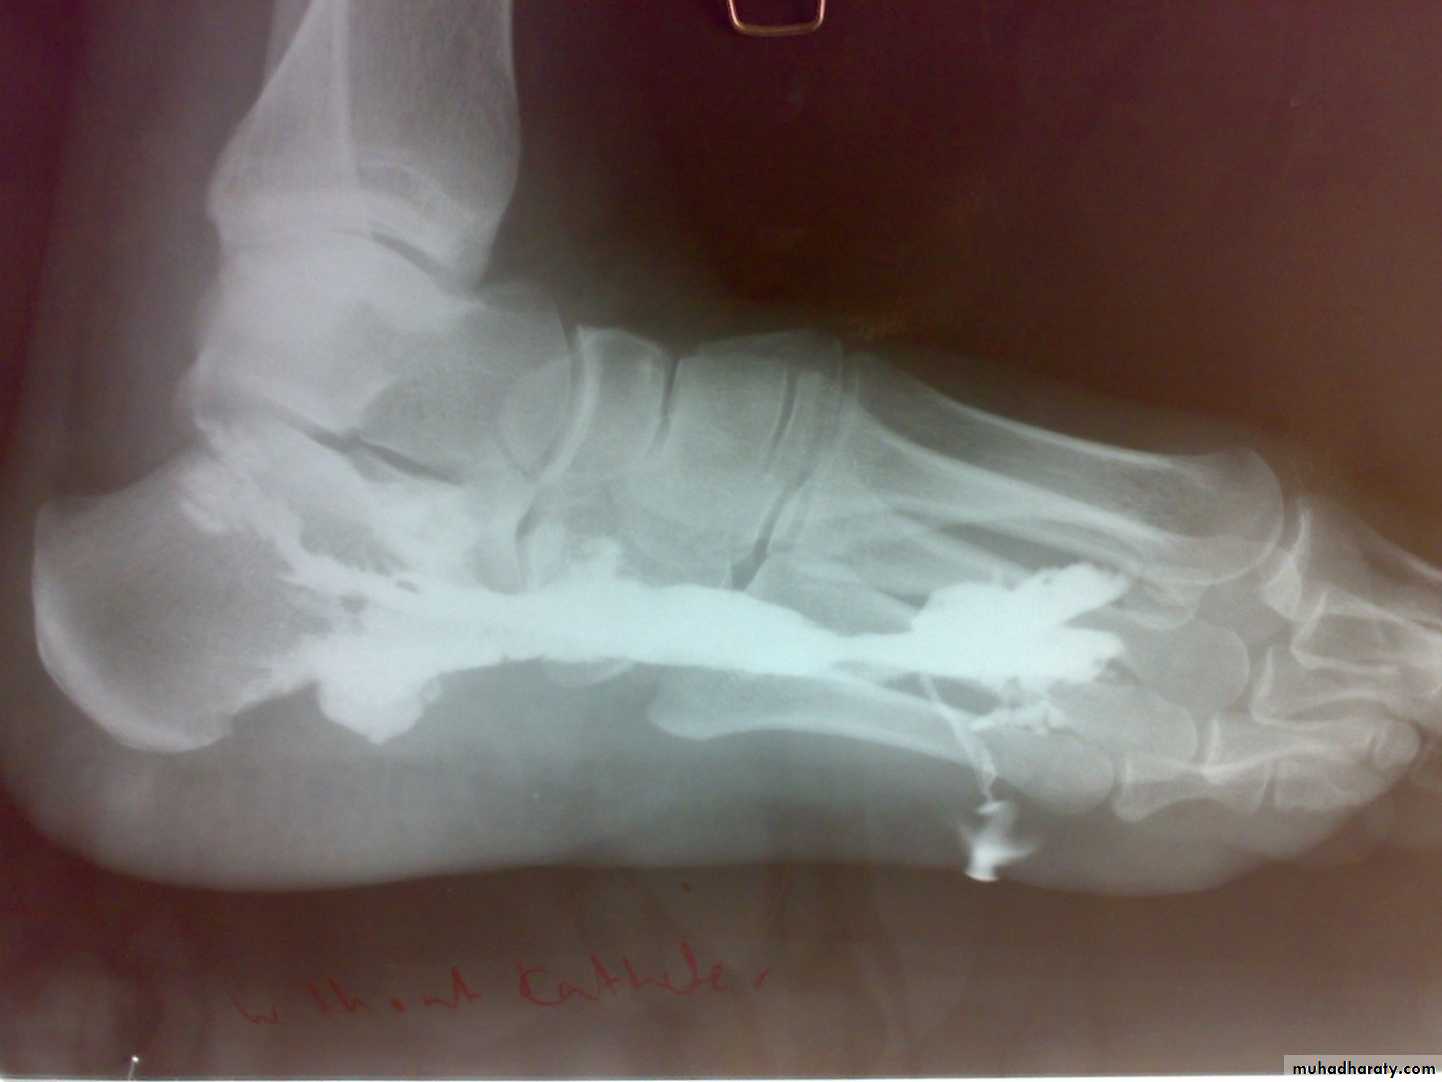

Radiological features

early changes:Soft tissue swelling, Periarticular osteoporosis

Loclized osteoprosis (Bone ends ‘washed – out’ or localized decalcification ).

Narrowing and irregularity of the articular ends.

Late changes:

Erosions of the subarticular cartilage.

cystic changes appeared.